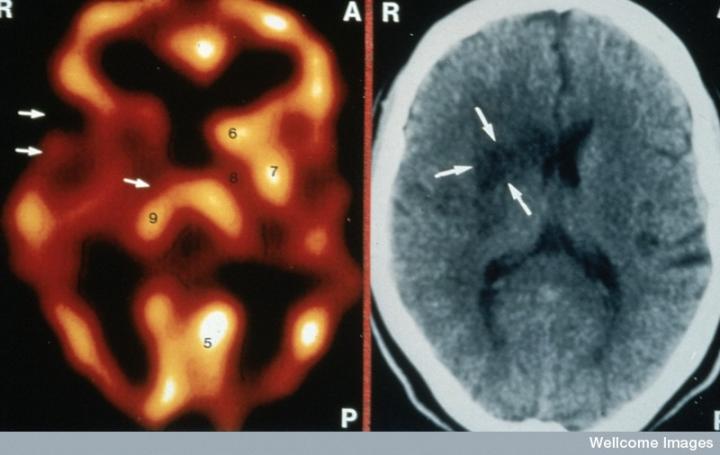

左側的血流圖比右側的X射線(xiàn)CT掃描顯示出更多的中風(fēng)損傷

慢性中風(fēng)患者的腦成像

CT掃描的主圖顯示左側有一些中風(fēng)損傷,由 Wellcome Images提供。Wellcome Photo Library提供的慢性中風(fēng)的附加圖像 ,Wellcome Images,QL 從胚胎干細胞培養的神經(jīng)元。Ying & A. Smith, Wellcome Images 和 Yirui Sun, Wellcome Images 移植的小鼠神經(jīng)干細胞。